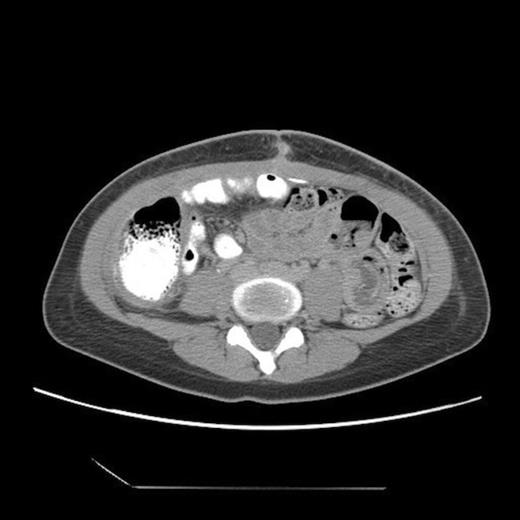

One-month follow up abdominal CT demonstrating recurrent formation of abdominal pseudocyst

The patient underwent laparoscopic cyst drainage with removal of the cyst wall. A total of 12.7L of fluid was drained. Culture results and routine labs were all negative. A post-operative CT demonstrated complete resolution of the fluid compartment (Fig. 4). The VP shunt catheter was initially left in the abdominal cavity. One month later, however, she developed significant recurrence of fluid collection (Fig. 5) and lethargy from malfunction of the VP shunt. The recurrent fluid was drained under ultrasound guidance, and her abdominal shunt catheter was removed. A new shunt catheter was placed in the right atrium, and the patient made a full recovery without any further complications.